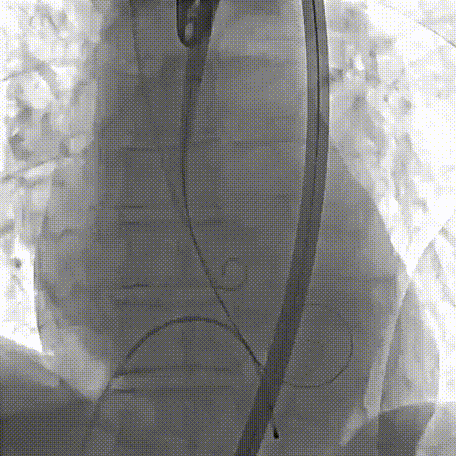

2026年伊始,TaurusTrio经导管主动脉瓣系统在复旦大学附属中山医院,浙江大学医学院附属第二医院,中国医学科学院阜外医院,首都医科大学附属北京安贞医院,四川大学华西医院等多家临床中心成功开展上市后全国首批植入。这不仅是TaurusTrio正式走向广泛临床应用的重要里程碑,更标志着中国单纯主动脉瓣反流介入治疗正式迈入了“心键合璧”的全新纪元。